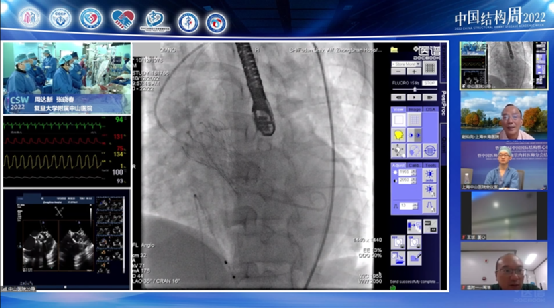

本届结构周由复旦大学附属中山医院主办,10月10日至10月14日葛均波院士、周达新主任领导的中山医院结构团队在短短5天之内,向国内及国际会场直播演示了18台高质量的手术(含3台录播):5台经导管主动脉瓣置换,1台经导管二尖瓣缘对缘修复(TEER),2台经导管三尖瓣成形(K-Clip),2台经导管三尖瓣置换(LuX-Plus),1台经导管肺动脉瓣植入(PPVI)3台左心耳封堵(LAAC),2台可穿刺房间隔封堵器(ReAces)房缺封堵,1台经导管卵圆孔(PFO)封堵,1台经皮球囊肺动脉成形(PBPA)。不仅全面覆盖四个心脏瓣膜:主动脉瓣、二尖瓣、三尖瓣、肺动脉瓣;涵盖新近结构领域的主流术式:心源性脑卒中的预防(左心耳封堵、卵圆孔未闭封堵),还有慢性血栓栓塞性肺动脉高压的球囊扩张,以及传统先天性心脏病的新概念器械:可穿刺房间隔封堵器的直播亮相,吸引来云端数十万观众的点击关注。

这18台手术各有千秋,看点十足,首先,有同一术式不同器械的对比:中山医院团队在经导管主动脉瓣置换(TAVR)频道就分别直播展示了HanchorValve, TaurusElite、Evolute Pro 、Venus-A plus,VitaFlow II等新型器械应用特点。其中,HanchorValve为全球首个带有锚定件的球囊扩张瓣膜,由中国心血管医生创新俱乐部的成员发明、葛均波院士作为PI在全国进行多中心临床试验,此次转播为该瓣膜首次手术直播。左心耳封堵频道也分别展示了Watchman FlX,LACbes和Lambre左心耳封堵器的各家所长,让观众觉得收获满满!也有同一疾病不同治疗术式的对比:中山医院此次就国际最前沿的三尖瓣反流两种介入治疗:三尖瓣瓣环成形(K-Clip)和瓣膜置换(LuX-Plus)分别进行了直播展示,并且对三尖瓣反流的特点和两种介入治疗术式的适应征进行了深入的分析和对比,得到了业内同行的广泛赞誉!此外,传统先天性心脏病的新概念器械:世界首个可穿刺房间隔封堵器(ReAces)的直播亮相也是此次中山医院团队直播的一大亮点:直播中展示出封堵器房间隔成形服帖,金属含量少,预留可穿刺通道的特点获得国内专家广泛关注。